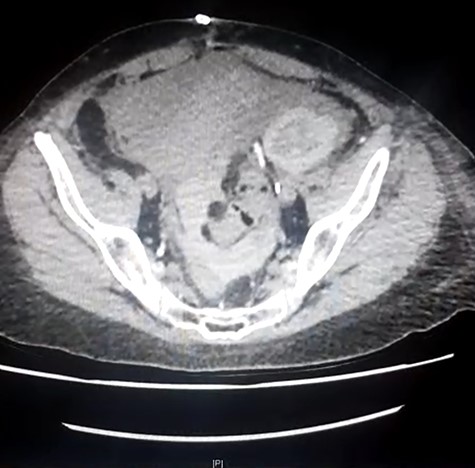

She presented to her local hospital due to sudden onset of severe abdominal pain with associated nausea, vomiting and diarrhoea. She was tachycardic though normotensive on presentation and found to have generalized severe abdominal pain. CT imaging revealed an SBO with an evidence of ischaemia as well as an obstructed ureter and renal collecting system within the allograft (Fig. 1). She underwent laparotomy, division of band adhesion in the left pelvis and 1.2 m of small bowel resected due to ischaemic necrosis with an end-to-end hand sewn anastomosis.

Initial CT demonstrating SBO and obstructed renal allograft/ureter (double obstruction).